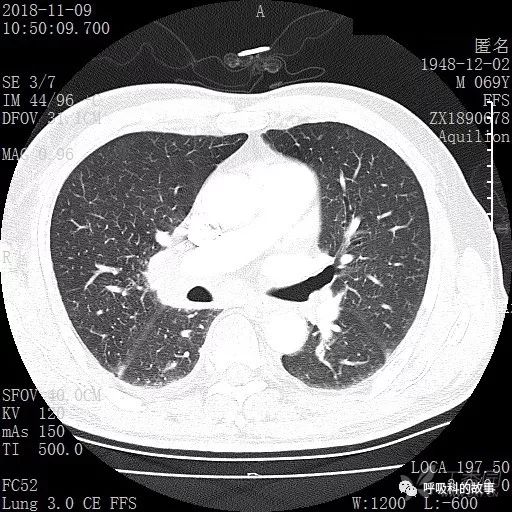

胸部增强CT示右肺门占位伴远端阻塞性肺炎,纵膈、右肺门、右侧颈根部、右侧腋下及肝门部肿大淋巴结。两侧胸腔少量积液。

肺窗CT